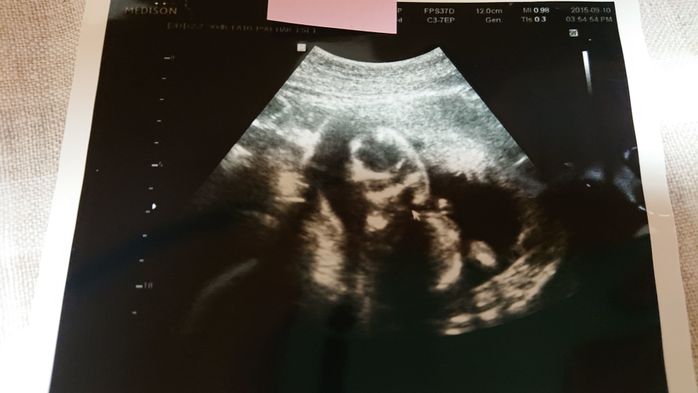

《妊娠9週目のエコー写真》

前回のエコー検査から2週間が経った妊娠9週での健診。この2週間で医師もびっくりするくらい赤ちゃんが大きくなりました。「急に大きくなりすぎて予定日が確定しがたいな~」と告げる医師。3月上旬くらいという話だった予定日が、2月20日ごろに変更となりました。小さな小さな手足もできていて「人っぽくなってきた」と赤ちゃんの存在をより実感した1枚です。矢印の部分が手足です。